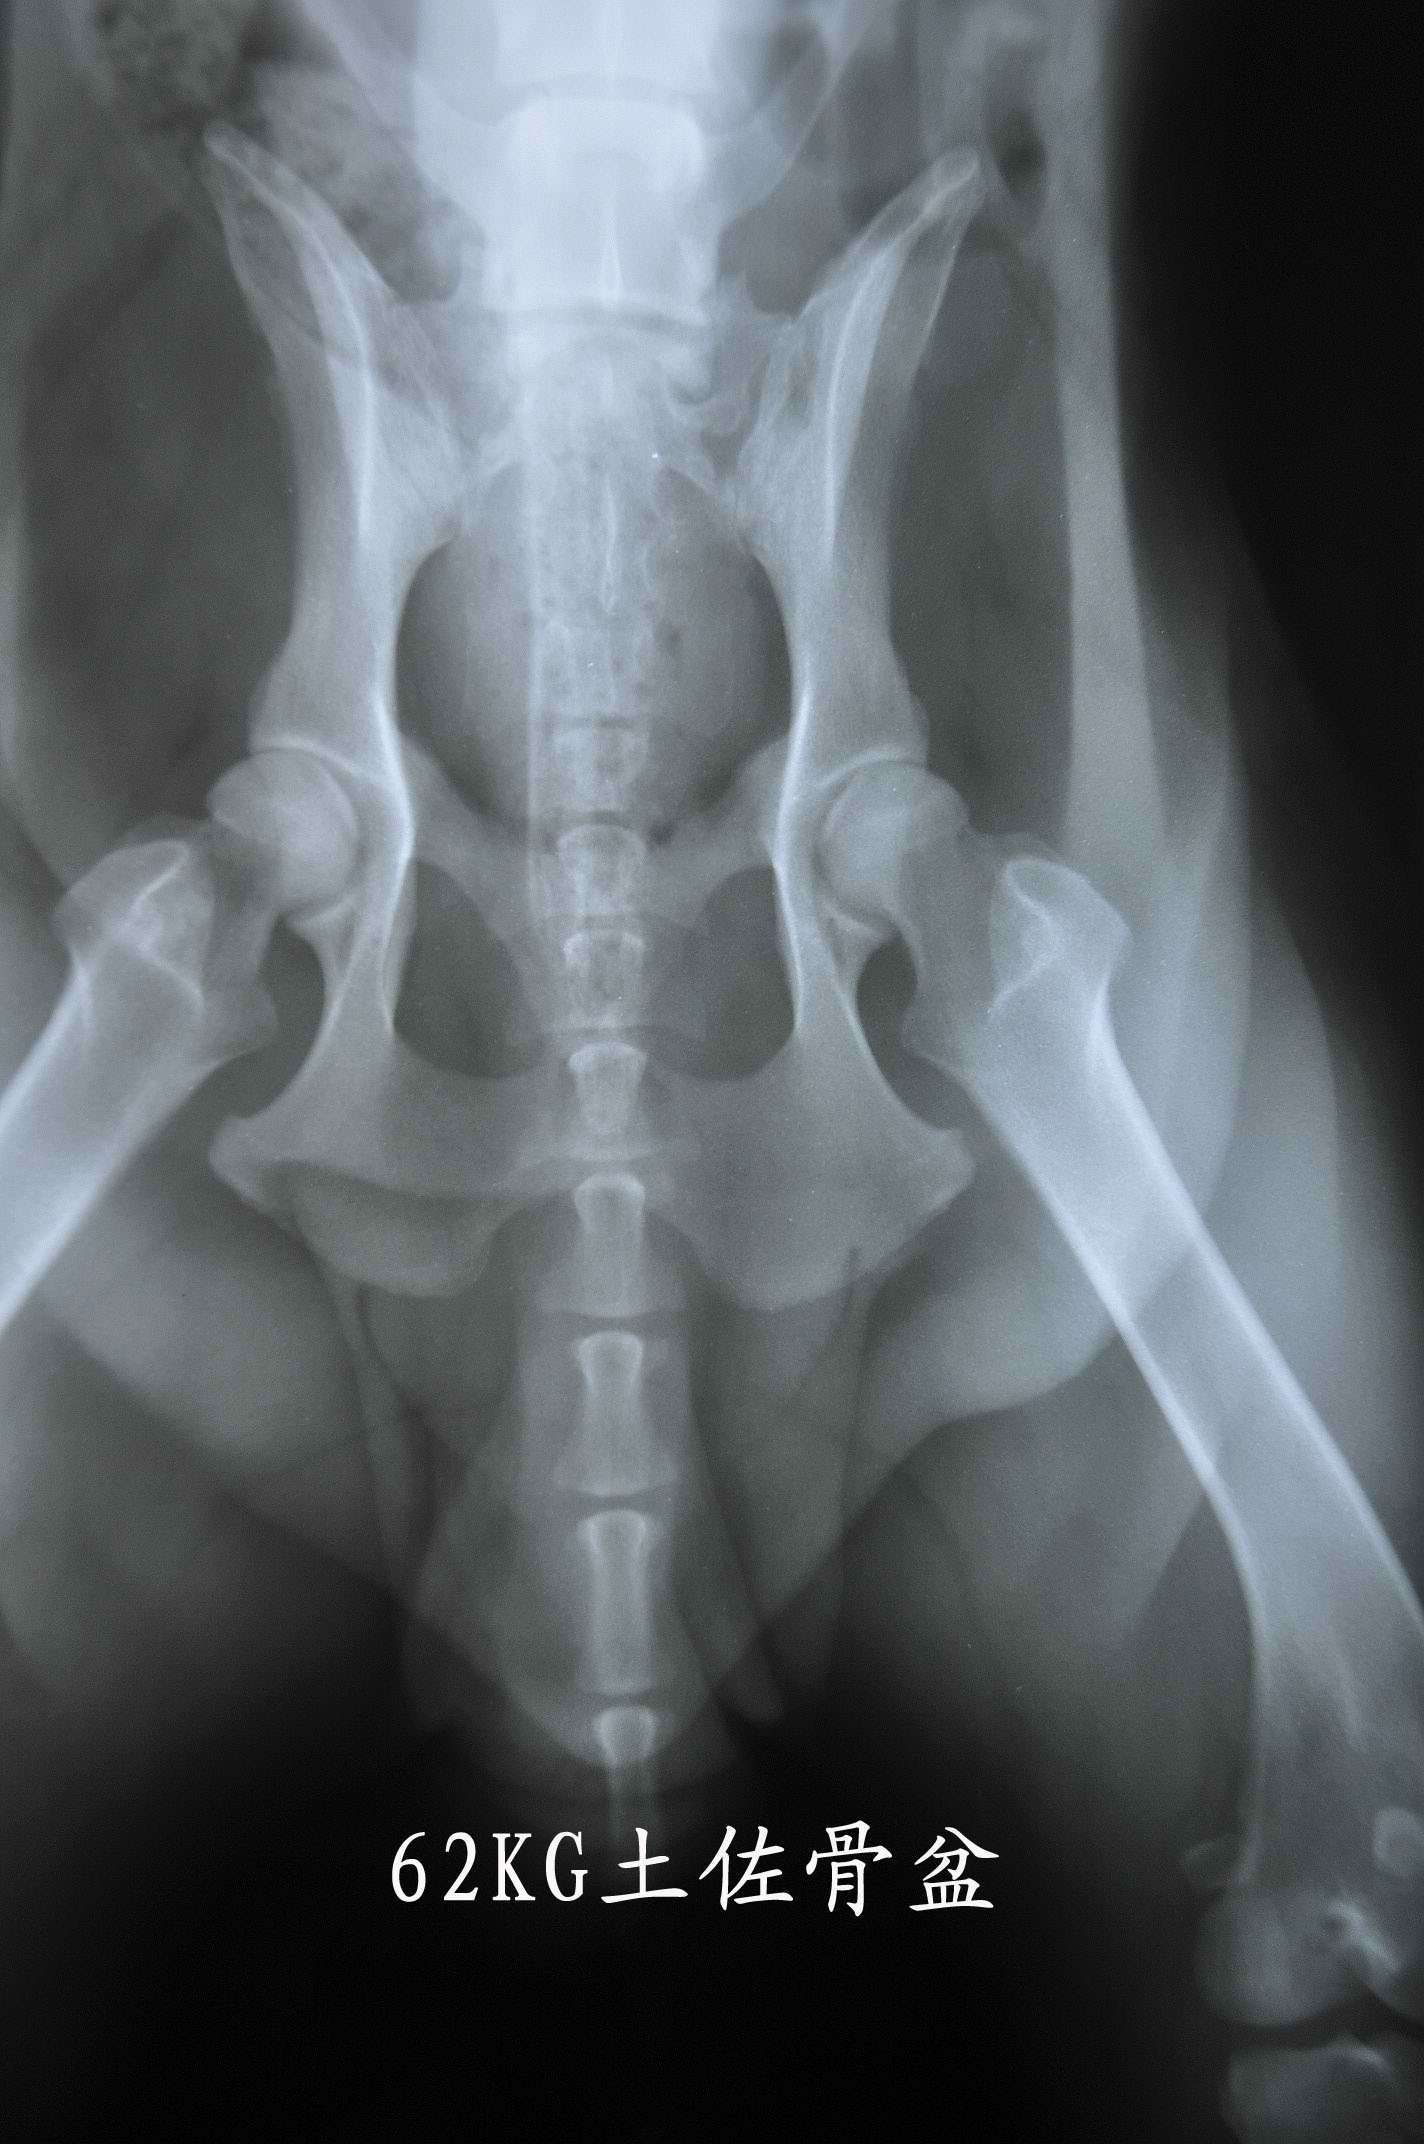

近有客户想要了解 下宠物X光机拍片的突显,以下使用我公司生产的宠物X光机拍摄的照片。 如果您需要采购宠物X光机。可以致电:0536-8322186或18953679166! 上一篇:上一篇:拍片机成像系统点片方案有哪些 下一篇:下一篇:如何区分CR拍片机和DR拍片机